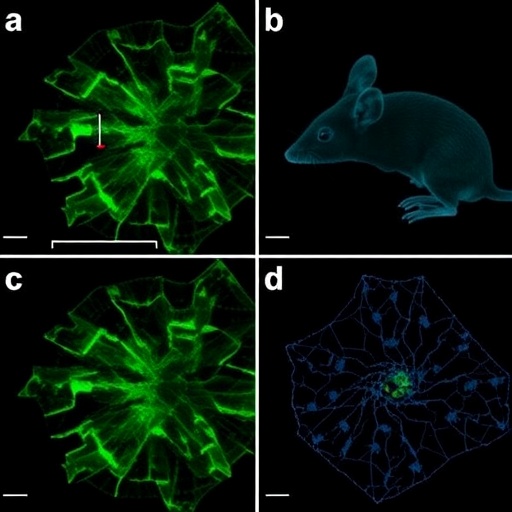

Caspase-4 Mice Show Cytoplasmic TDP-43, Aging Neuropathy

In a groundbreaking study poised to redefine our understanding of neurodegenerative diseases, researchers have uncovered compelling evidence linking the expression...